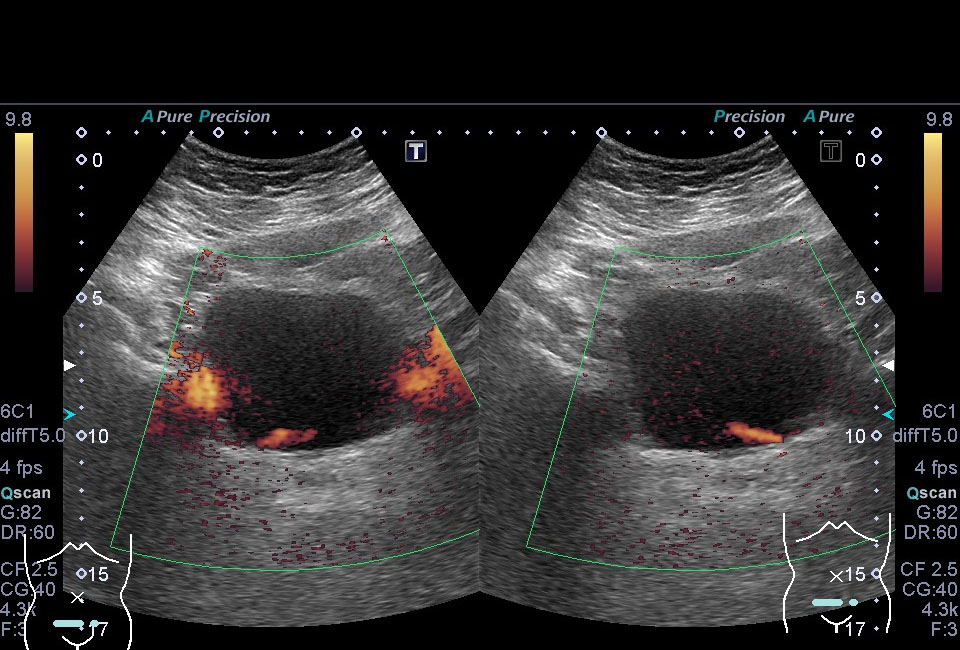

超音波(エコー)

下記など多くの診断ができます。

各項目をクリックすると診断画像が表示されます

超音波(エコー) 診断画像

- 腎細胞がん